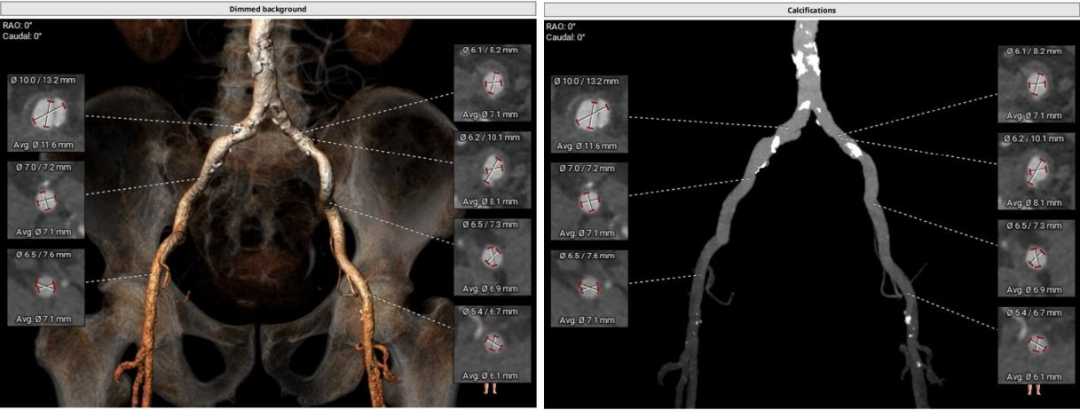

患者CT评估

三叶三窦式主动脉瓣

瓣环周长94.5mm,平均周长径30.1mm;

SOV瓦式窦:32.6mm *35.4mm*36.9mm ;

LVOT周长91.9mm,平均周长径 29.2mm。

STJ平面周长115.2mm;

升主动脉最大直径47.6mm;

瓣叶重度钙化合并增厚,钙化分布不均,主要集中于左冠窦内。

HU953 积分862mm²。

左冠高度14.7mm 右冠高度15.1mm;

瓣口对应瓣叶稍冗长,术中须注意冠脉风险。

心脏水平夹角67°,横位心;

左室腔内径尚可,心室壁增厚明显。

主动脉弓夹角及弓距可,外周血管入路无明显迂曲。

右侧髂总动脉自发夹层7mm。